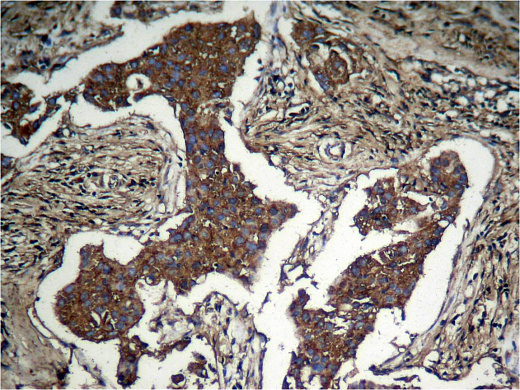

• применение – ICC/IF, IHC-P, WB;